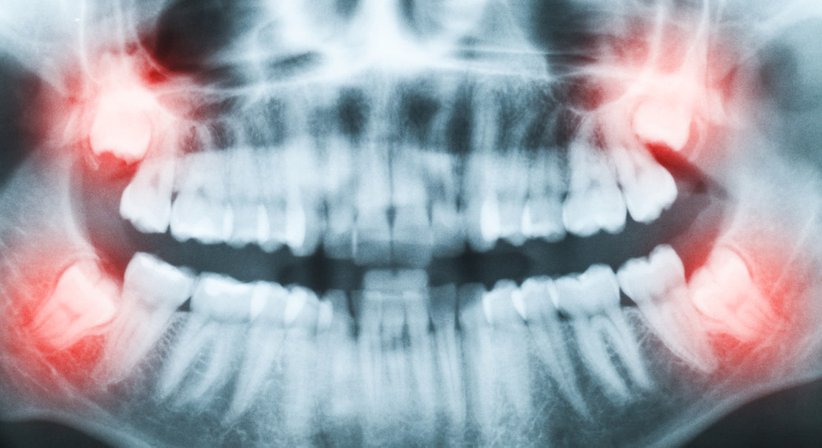

Weisheitszähne brechen in der Regel erst im Erwachsenenalter durch. Zu dieser Zeit verfügen sie jedoch häufig über zu wenig Platz im Gebiss. Die Folge: Sie liegen schräg und können nicht normal wachsen. In vielen Fällen bleiben die Weisheitszähne auch vollständig im Kiefer eingeschlossen oder brechen nur teilweise durch. Oftmals drücken sie auf benachbarte Zähne und können diese auch schädigen.

Bevor retinierte oder verlagerte Weisheitszähne Schmerzen und Entzündungen verursachen, sollten sie rechtzeitig gezogen werden.